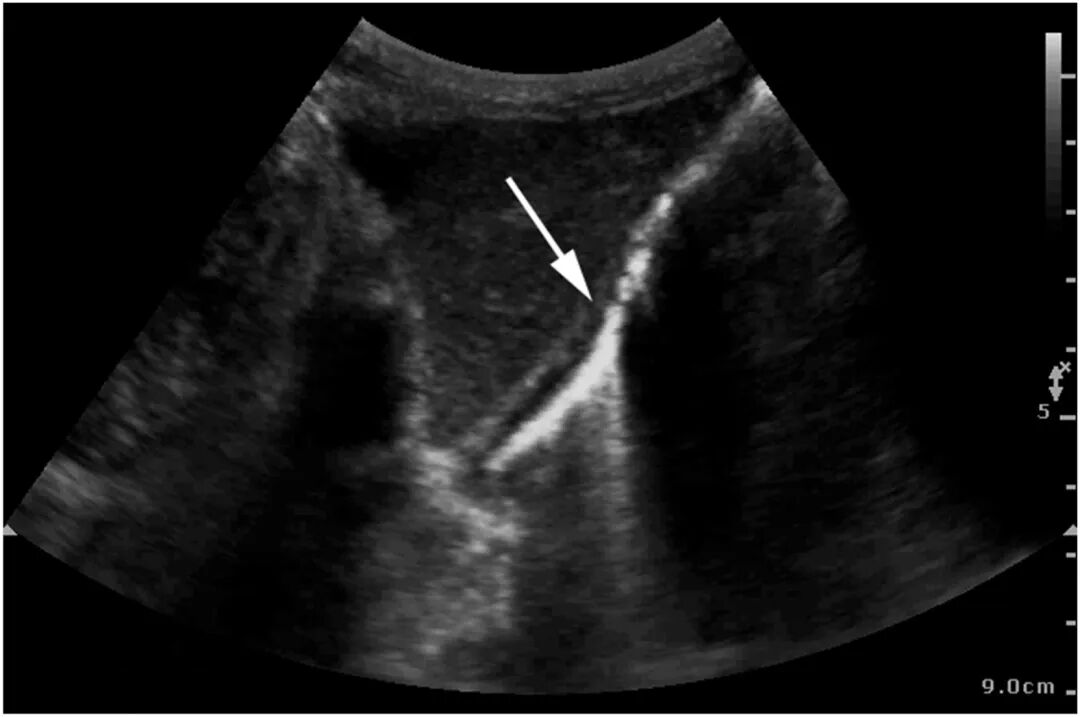

ICU第6日,患者因肠内营养不耐受出现轻微腹胀,C反应蛋白升高(199.69 mg/L),提示感染加重。鉴于病情变化,行床边即时超声检查,显示胃壁内出现“彗星尾”伪影(见图2、图3)。随后行腹部CT证实胃壁内气体积聚(图4)。

图2 床旁超声剑突下切面显示胃壁"彗星尾"伪影